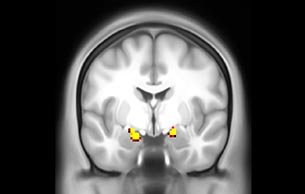

The fMRI pulse sequence was a single shot FFE echo planar acquisition using MultiBand SENSE factor 5, dS SENSE factor 1.25, isotropic voxel size 2.7 mm, 50 transverse slices, TR 700 ms, TE 30 ms, flip angle 52 degrees, 765 dynamic scans, total scan duration 9:01 minutes. Image provided by Matthan Caan, PhD, Assistant Professor at the AMC.

Default mode network as discovered by resting state fMRI in one participant of the ALFA cohort [7]. rs-fMRI allows us to find networks of brain regions with highly correlated activity and sustaining distinct brain functions. The default mode network (in warm color scale) is active when the brain is focused on introspective thinking and has been shown to be altered in Alzheimer’s. Interestingly, brain areas of this network are known to show abnormal levels of one of the pathological hallmarks of Alzheimer’s (b-amyloid deposition) in preclinical stages. We want to better understand the alterations of these brain networks in preclinical stages of Alzheimer's and explore their potential use as biomarkers.